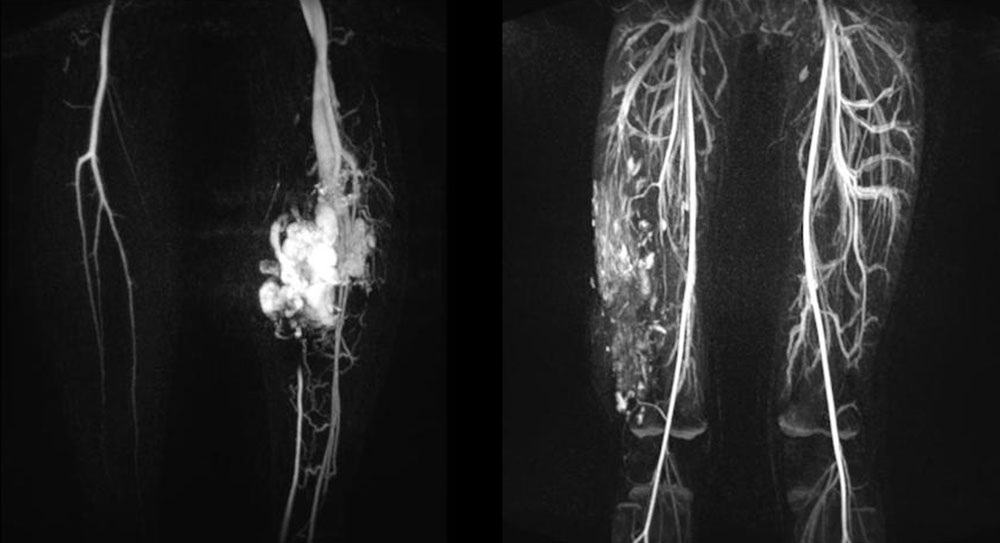

Arteriovenous malformations (AVM) and the even rarer congenital arteriovenous fistulas make up the smallest proportion of simple vascular anomalies, at approx. 6%. They consist of a malformed vascular area, which in the case of arteriovenous malformation manifests itself most often as multiple, often reticular, direct arteriovenous shunts (nidus), or multiple fine arterial vessels directly connecting to an enlarged draining vein bypassing the normal capillary bed. In the case of arteriovenous fistulas, by contrast, there is a single direct arteriovenous shunt connection. This shunt represents a short circuit of the arterial (inflow) and venous (outflow) vascular system, bypassing the capillary bed. This shunt-related very fast blood flow (fast-flow malformation) often makes the lesions feel warm and even pulsatile through the skin. The skin overlying the lesion is often red. AVMs are among the fast-flow malformations that, depending on their clinical manifestation and biological activity, certainly pose the greatest challenge to patient and physician because they are difficult to treat and often recur.